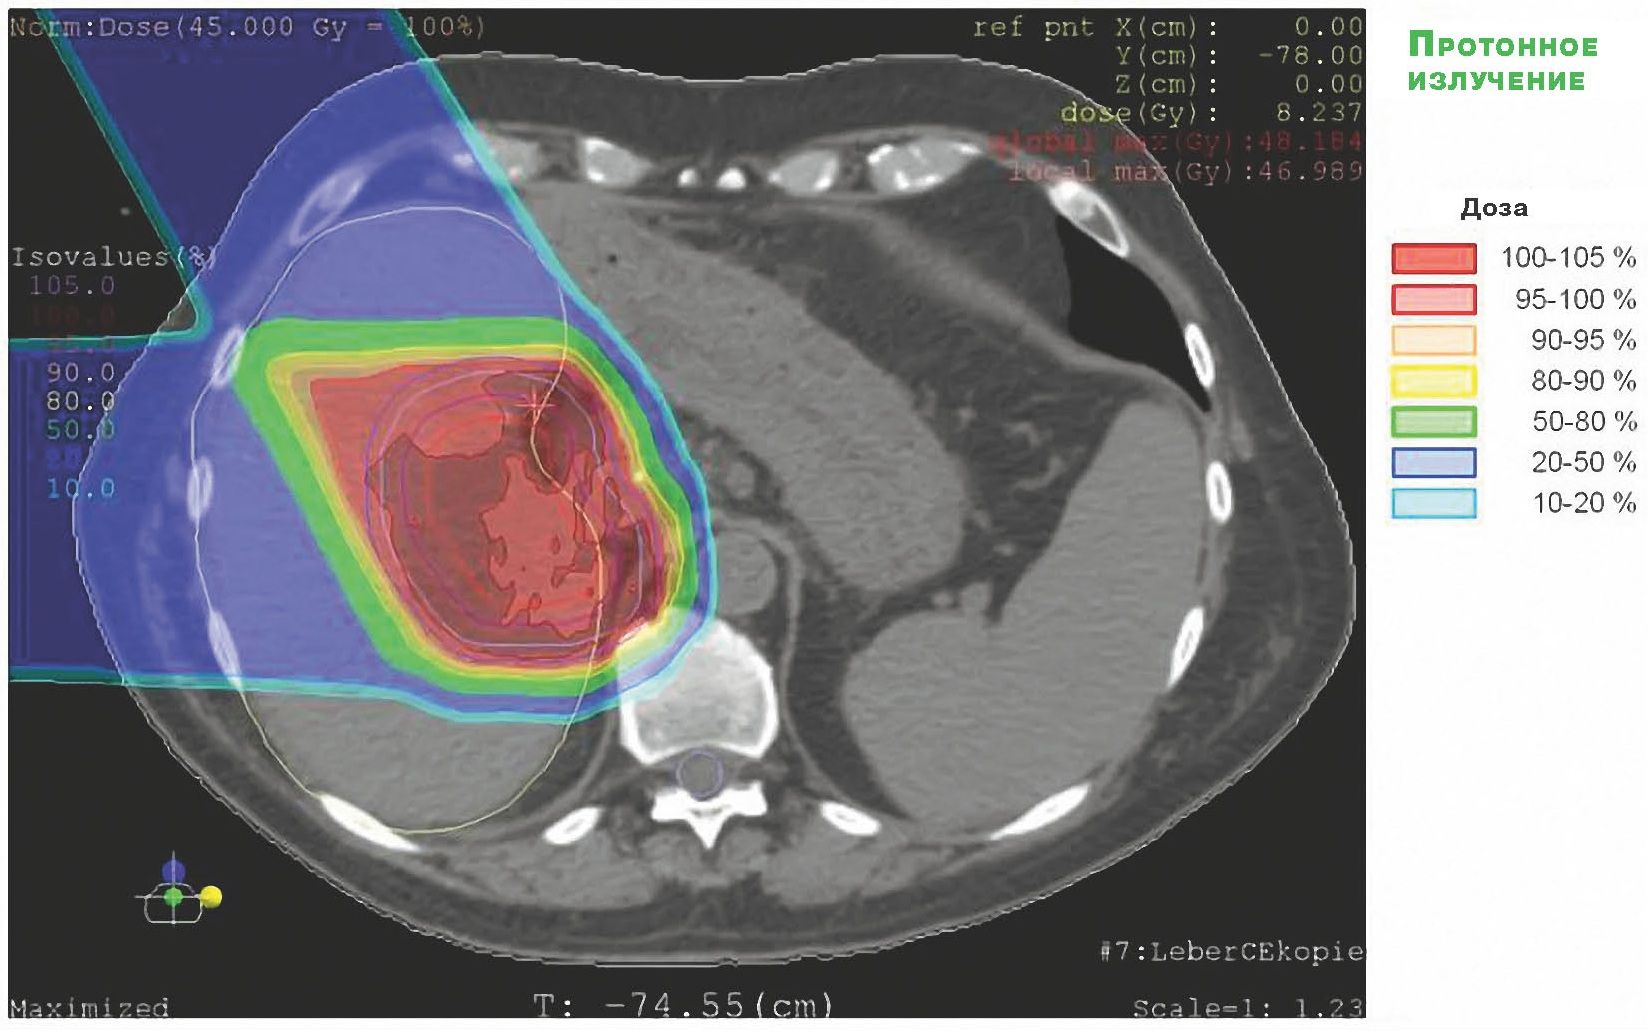

Второй шаг: информацию о форме и размерах опухоли в цифровом виде вводят в трехмерную компьютерную систему планирования облучения. Врач-радиолог обозначает на каждом томографическом срезе контур мишени и структуры организма, которые не должны быть повреждены (например, нервы). По намеченным врачом контурам компьютерная программа создает трехмерные модели структур. После этого врач-радиолог выбирает дозы и направления облучения (направлений может быть от двух до семи). Программа beams-eye-view («взгляд на мишень со стороны пучка») определяет форму поперечного сечения протонного пучка, которую должен воспроизвести коллиматор.

Третий шаг: изготовление фигурных коллиматоров и компенсирующих болюсов. По заданной форме поперечного сечения пучка подбирается материал цилиндра коллиматора (чтобы если нужно – ослабить пучок, поглотив в стенках цилиндра часть протонов) и рассчитывается форма его отверстия. Исходя из распределения назначенной пациенту дозы и границ протонного пучка по глубине мишени, рассчитываются и затем изготавливаются болюсы. Их форма должна учитывать неоднородность структуры тканей и органов пациента, расположенных на пути летящих частиц.

Четвертый шаг: сеансы облучения индивидуально подобранным с помощью трех предшествующих шагов пучком протонов. Перед началом сеанса всякий раз проводится тщательная дозиметрия пучка. Рентгеновская трубка, установленная за пациентом на оси пучка, проверяет точность положения пациента по отношению к протонному пучку. Если это положение не совпадает с точностью до миллиметра с тем, которое было рассчитано программой планирования, положение кресла с пациентом исправляется – облако протонов должно точно повторить обличье скопления раковых клеток.